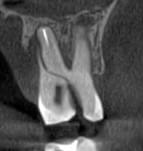

Ми розуміємо, наскільки важлива деталізація в ендодонтії та терапевтичному лікуванні.

Завдяки флагманському обладнанню PLANMECA, ми отримуємо знімки з мінімальним рівнем шумів та

високою роздільною здатністю, що дозволяє чітко візуалізувати морфологію кореневих каналів,

приховані каріозні порожнини та стан періапікальних тканин.